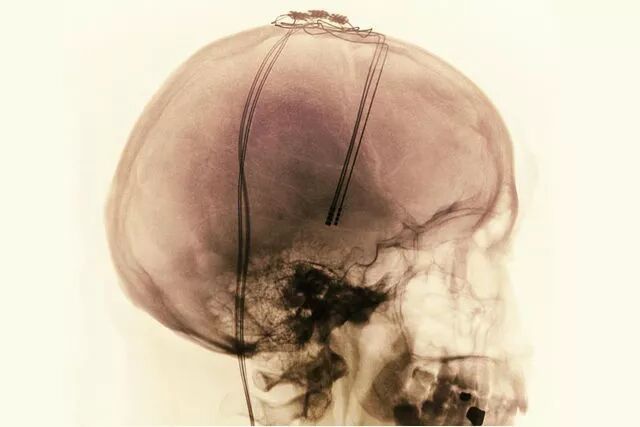

(图片来源于网络,DBS手术需要精确定位靶点,避免开机后患者出现副反应)

(DBS术后)